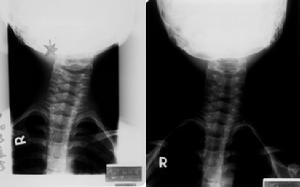

2、X線檢查,有利於鑑別不同原因造成的斜頸,如枕頸部畸形所致的骨性斜頸和自發性寰椎鏇轉性半脫位引起的斜頸一般不會產生胸鎖乳突肌的攣縮和腫塊,後者多有輕微外傷或上呼吸道感染病史。

斜頸(1)先天性骨性斜頸 本症多系先天性枕頸部畸形所致,包括短頸畸形、顱底凹陷、半椎體畸形、寰枕融合及齒狀突發育畸形。上述疾病可造成斜頸及面部不對稱,但一般不會產生胸鎖乳突肌的典型條索狀攣縮帶及腫塊,X線檢查可明確上述診斷。

(3)自發性寰樞椎鏇轉性半脫位寰樞椎鏇轉性半脫位同樣可以引起斜頸,但此病多有輕微外傷或上呼吸道感染病史,主要表現為頸部鏇轉運動受限及頸部疼痛症狀明顯,胸鎖乳突肌仙無緊張條索帶,X線檢查可鑑別。

(4)頸椎結核頸椎結核可使胸鎖乳突肌痙攣而產生斜頸,但此類患者頸部疼痛明顯,頸部活動明顯受限,下頜偏向患側,X線檢查可明確診斷。